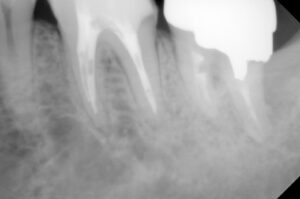

と痛みの部分を小さいレントゲンで確認

冠を被せた第二大臼歯の問題以上に、痛みは

第一大臼歯の詰め物の下が虫歯になっている

ことを説明し、処置内容と概算費用をつたえ

2026年1/8に左下第一大臼歯の痛み増幅で来院

温冷刺激痛と咬合痛まで起こしているので

神経の処置が必要で被せ物まですると

レントゲンでは神経の詰め物の状態の違い→